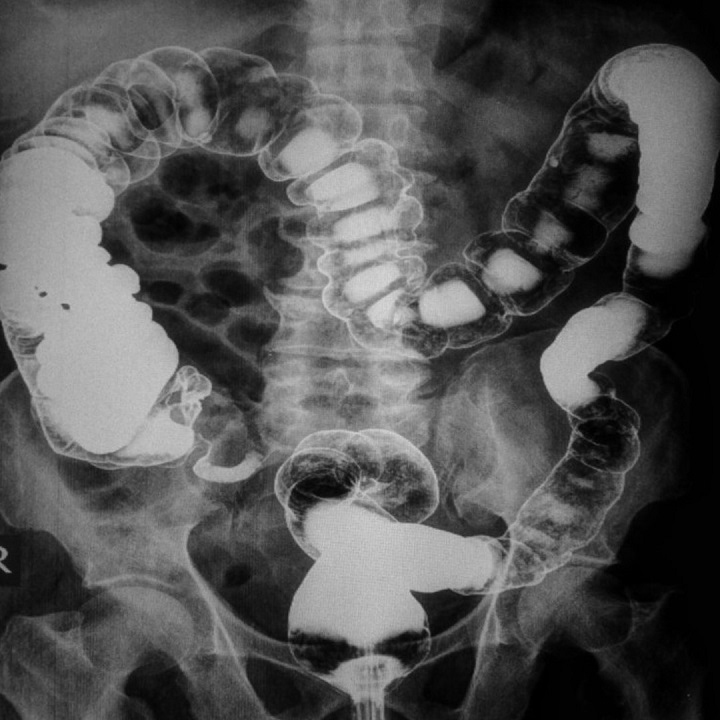

Étkezések után gyakran szorul össze a gyomrod? Kiütéses leszel a reggelitől? Bizonyos ételek hatására nehezebben lélegzel? Ezek a tünetek valószínűleg ételallergiából fakadhatnak. Most kiderítheted, milyen összetevőket nem bír a szervezeted.